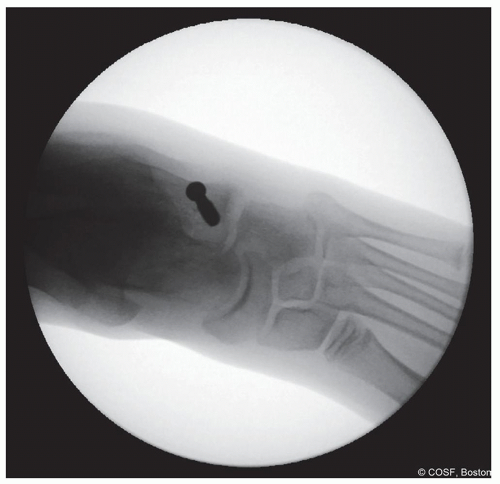

Confirm position of screw on fluoroscopy—anteroposterior (AP) and lateral (Figures 28.12 and 28.13)

Figure 28-12 ▪ Lateral view fluoroscopy showing the screw in the proper location. (Courtesy of Children’s Orthopaedic Surgery Foundation.)

Figure 28-13 ▪ Anteroposterior view fluoroscopy showing the screw in the proper location. (Courtesy of Children’s Orthopaedic Surgery Foundation.)